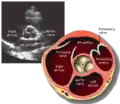

This view is obtained in the same window as the parasternal long, but with the probe rotated 90°. In this view, the aortic valve is seen in cross-section with the right ventricular inflow & outflow tracts visible with the tricuspid valve as well. Pulmonary valve is not visible in this view. Both the right and left atria are visible.

The standard PSAX view is at the level of the aortic valve, but moving the probe along the long-axis can review the LV outflow tract, LV at the base, and LV at the midsection.

Structures visible:

- Aortic valve in short-axis

- Aortic valve dysfunction, aortic sclerosis/stenosis

- Tricuspid valve in long-axis

- Pulmonary valve in long-axis

- Right ventricle, including inflow and outflow tracts

- Left ventricle in short-axis

- Closer to the base can reveal the left ventricular outflow tract

- At the level of the base can show the movement of the mitral valve leaflets in short-axis

- At the level of mid-LV can show papillary muscles